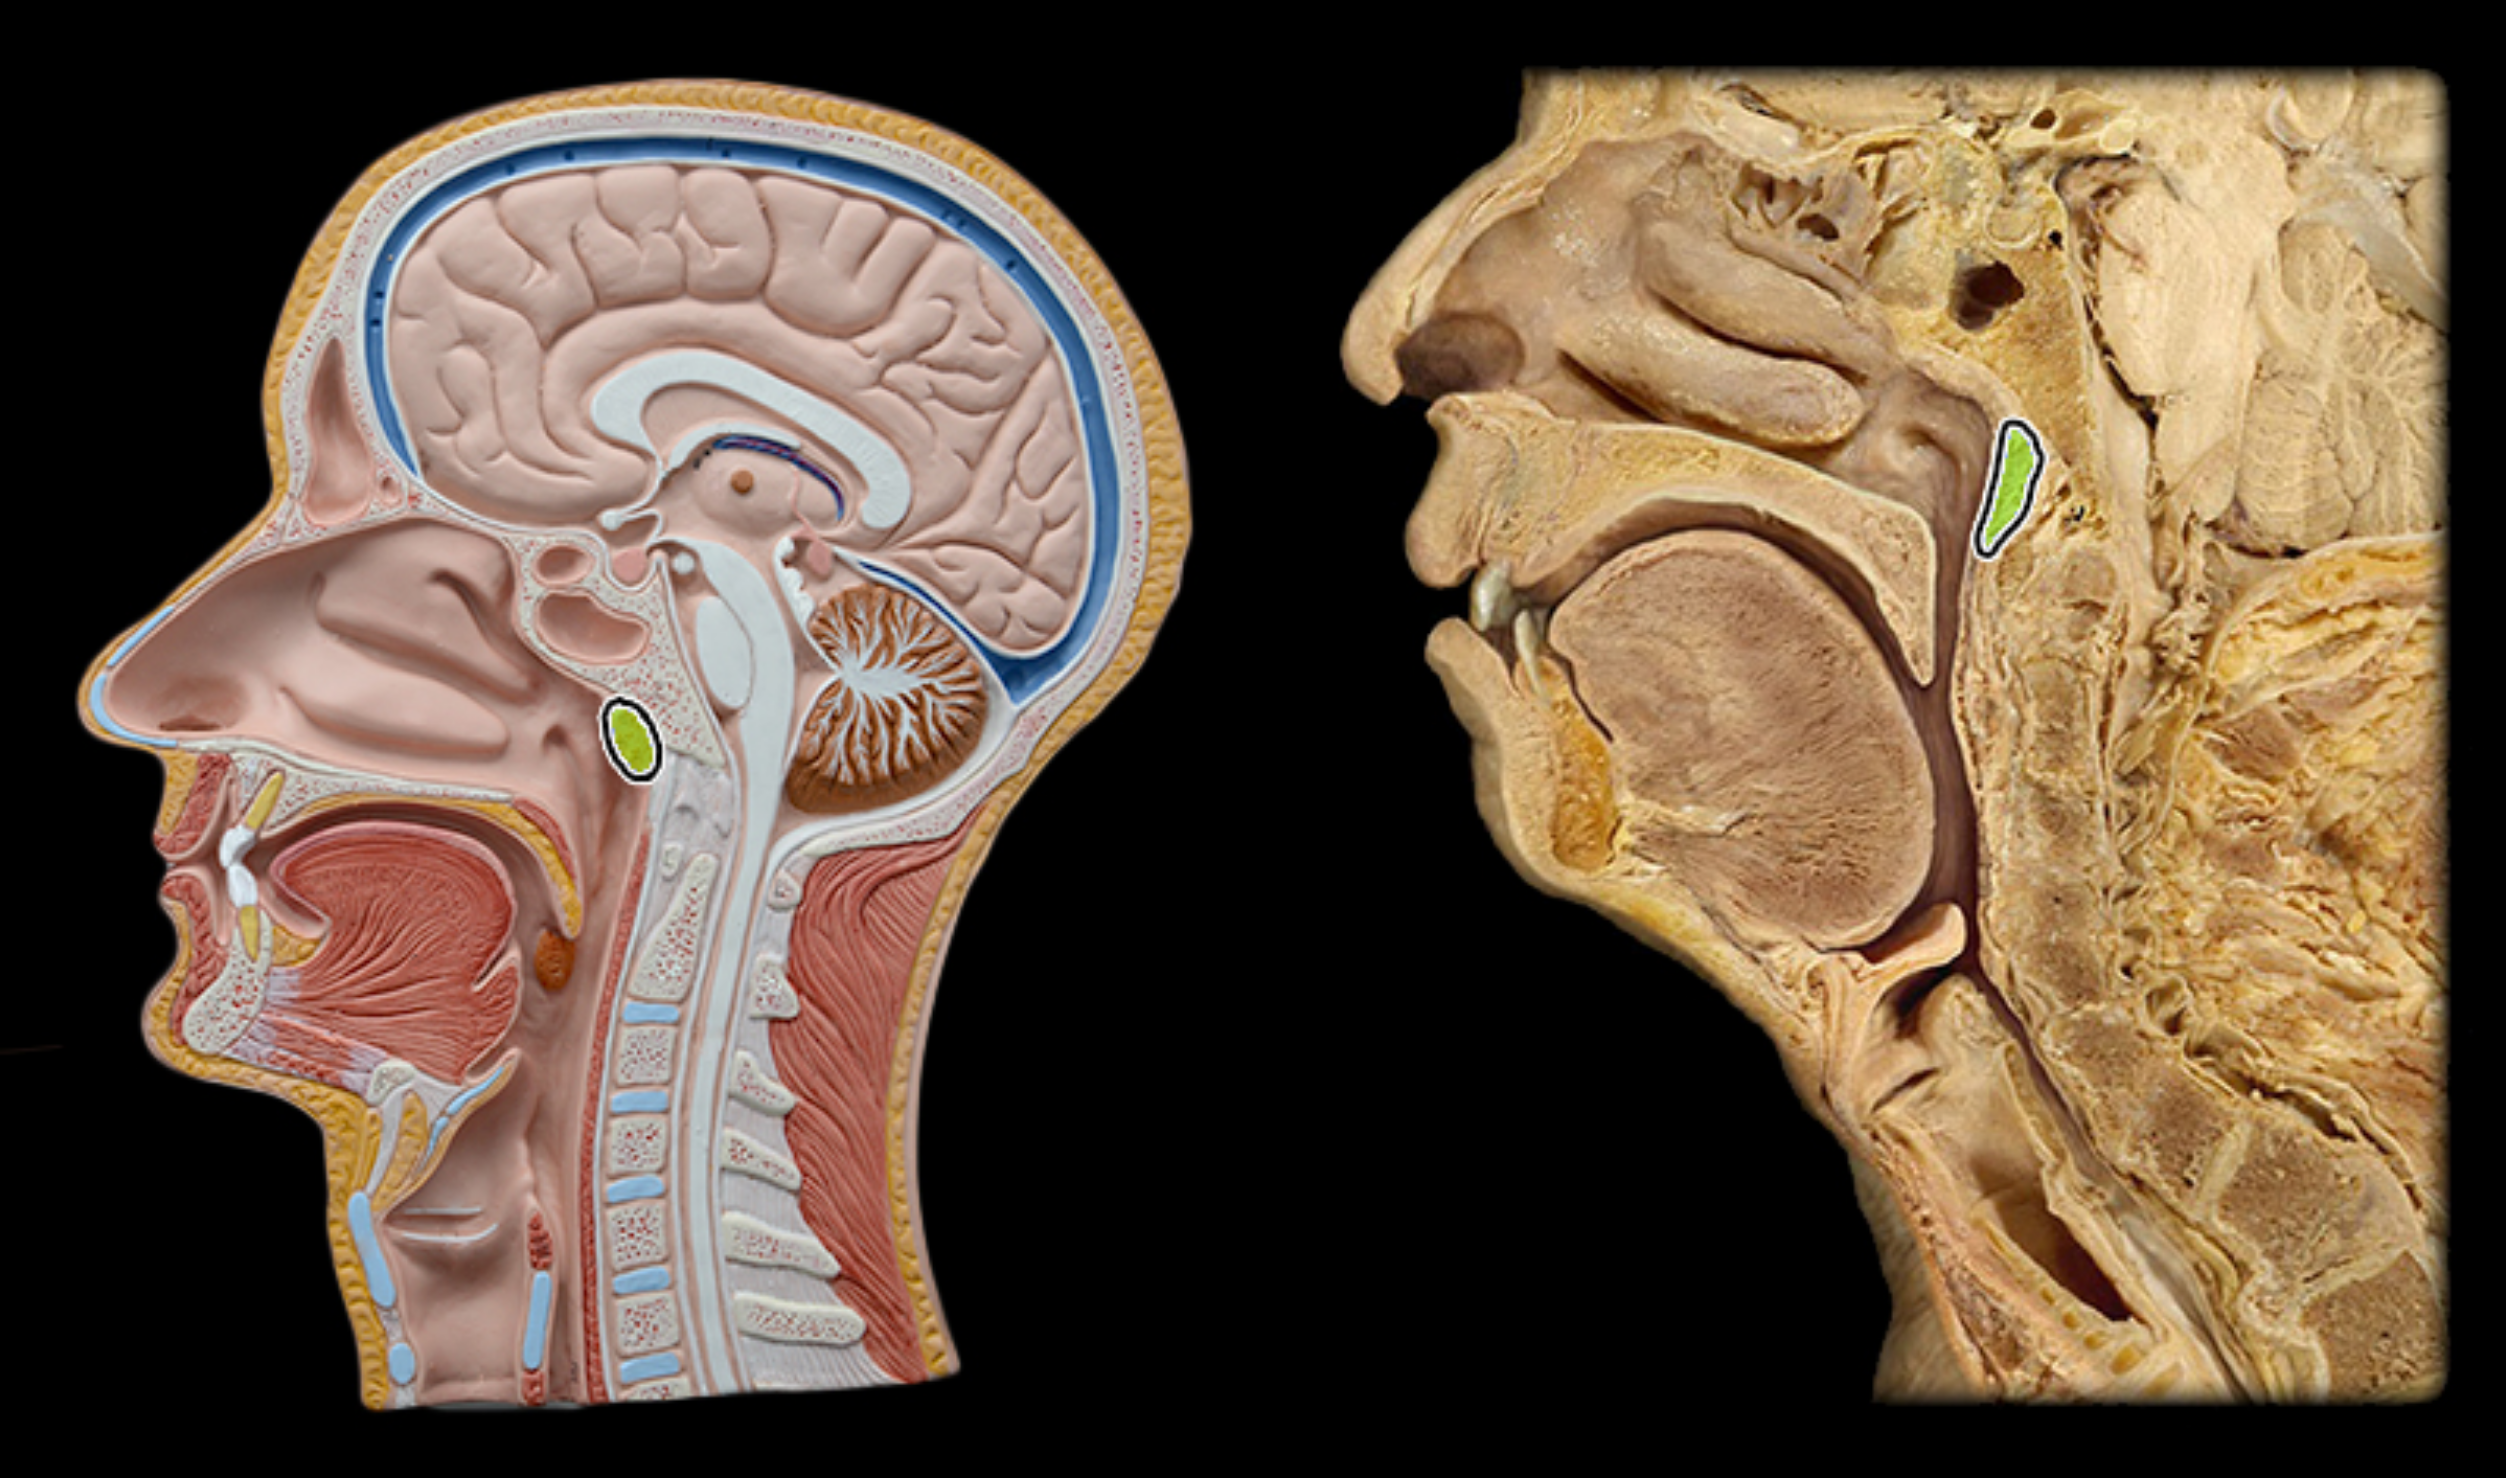

Pharyngeal tonsil

Palatine tonsil